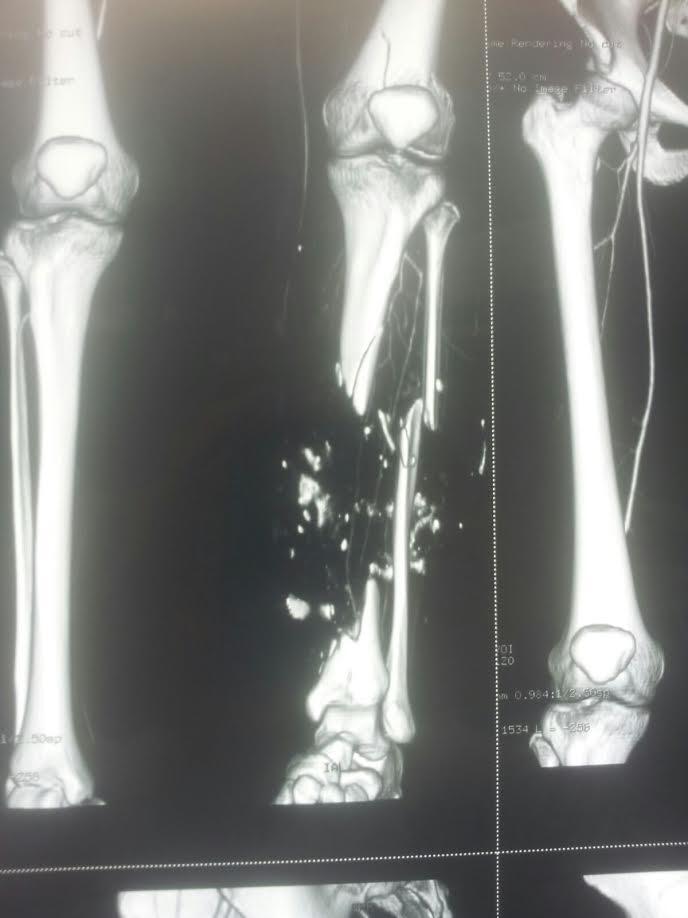

Pozzuoli – Al Santa Maria delle Grazie i medici hanno fatto un piccolo miracolo: invece che amputare una gamba a una paziente giovane, vittima di un grave incidente, hanno portato a termine un intervento di altissima complessità: un trapianto di tibia da cadavere con ricostruzione plastica dell’arto e utilizzo di cellule staminali. L’intervento, durato 13 ore, si è svolto qualche giorno fa ma solo ora viene reso noto, alla luce del buon esito della degenza. Intorno al tavolo operatorio ha lavorato un’equipe multidisciplinare guidata dal primario dell’ortopedia del Santa Maria delle Grazie, Pasquale Antonio D’Amato e composta da un chirurgo plastico, due anestesisti e tre ortopedici.

La paziente era arrivata in Pronto Soccorso a seguito di un grave incidente stradale nel quale aveva subito la frattura del femore sinistro e la quasi completa disintegrazione della tibia; le gravi ferite alla gamba avevano orientato i medici del Pronto Soccorso a chiudere i vasi sanguigni aperti per evitare il dissanguamento. Questa scelta, necessaria per salvare la vita, aveva determinato la necrosi dei tessuti, tanto da rendere praticamente obbligatoria la scelta dell’amputazione dell’arto.

“Il trapianto della tibia da cadavere era l’ultima opzione all’amputazione. – dice il dott. d’Amato – Si trattava di una scelta rischiosa, data la grande quantità di complicanze possibili. Nel corso dell’intervento abbiamo rimosso i tessuti morti, inserito 30 centimetri di tibia da trapiantare aumentandone la compatibilità e la capacità di attecchimento con un impianto di cellule staminali prelevate dal bacino. Abbiamo poi ricostruito i muscoli e la pelle attraverso un autotrapianto da muscoli dorsali, rivascolarizzato il tutto ricostruendo il sistema artero- venoso. Ci siamo orientati per un intervento del genere perché, nonostante le condizioni disperate della tibia, il piede era in buona condizione grazie alla miracolosa integrità delle due arterie principali della gamba. Ringrazio tutta l’equipe per il lavoro di assoluta eccellenza realizzato”.